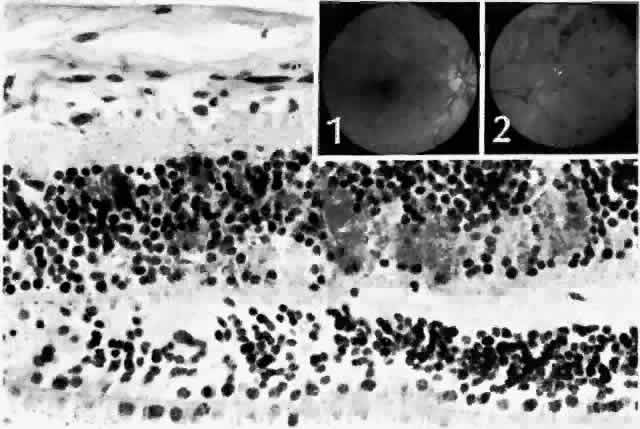

In some patients, the cystoid spaces can coalesce, forming lamellar or full-thickness macular holes.42 Other nonproliferative changes include intraretinal hemorrhages. Flame-shaped hemorrhages occur in the nerve fiber layer, and dot-blot hemorrhages occur in deeper retina, in the outer plexiform and inner nuclear layers (Fig. 9).

Fig. 9. Dot and blot hemorrhages consist of small collections of blood in the inner nuclear and outer plexiform layers of the retina. Insets. Fundus appearance of dot (1) and blot (2) hemorrhages, respectively. (Main figure, H&E, × 260)